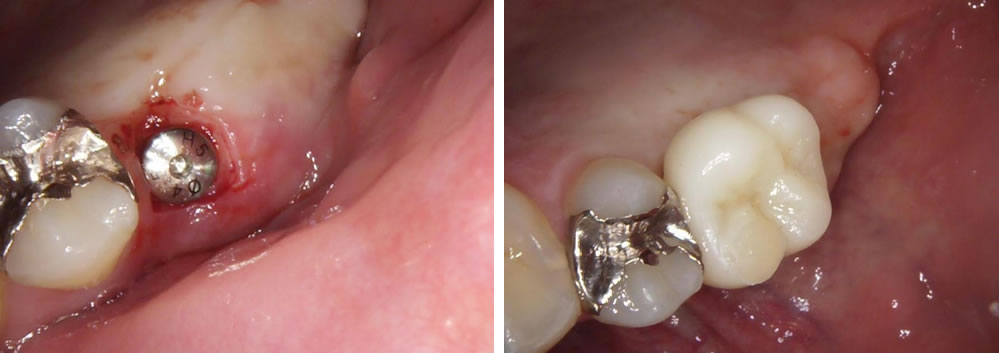

インプラント治療完了後の口腔内写真

最後は綺麗な歯を作成しセットし咬合の回復をしました。